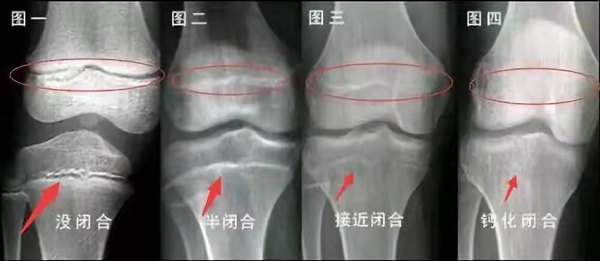

未成年時(shí)隨著年齡的增加骺軟骨端不斷骨化,骨骼就不斷增長(zhǎng)。當(dāng)骨骺線完全閉合時(shí)骨骼就停止生長(zhǎng),個(gè)子也就不再增長(zhǎng)了。一般骨骺端完全閉合的年齡是18~20歲左右。

骨骺線提前閉合最多見(jiàn)的情況是性早熟,而這也是很多醫(yī)生專家建議孩子進(jìn)行骨齡測(cè)量的原因之一。另外,在兒童時(shí)期大量補(bǔ)鈣也會(huì)使骨骺端提前過(guò)早閉合。

青少年一般什么時(shí)候骨骺閉合?

一般女孩是在16歲,男孩是在18歲。

一般來(lái)說(shuō),女孩的骨齡超過(guò)14歲,男孩的骨齡超過(guò)16歲,這時(shí)其骨骺線已接近閉合,基本沒(méi)有長(zhǎng)高的機(jī)會(huì)了。

因此,越早了解骨骺線閉合情況,越早干預(yù),孩子長(zhǎng)高的可能性越大。